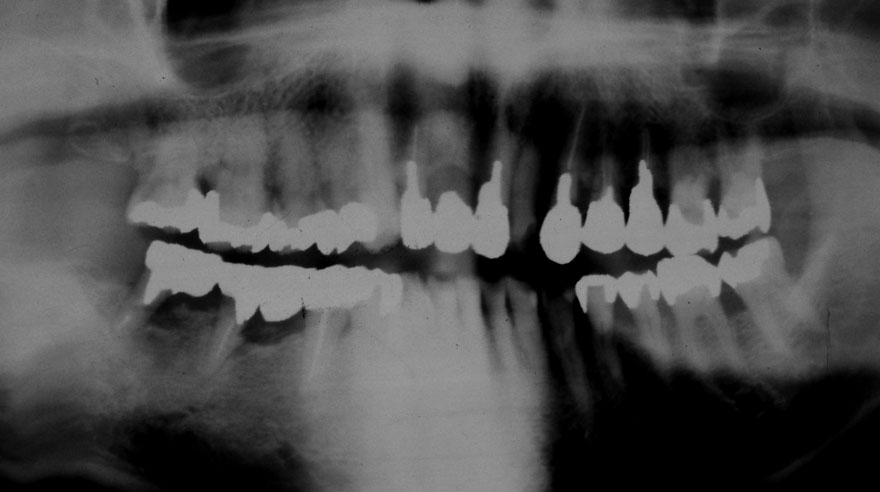

初診時 41歳 男性 平均歯槽骨喪失量:4.11mm

30年後 71歳

平均歯槽骨喪失量:3.70mm

30年間再生量:+0.41mm

年間再生速度:+0.014mm

(ケア頻度:1.27ヵ月ごと)